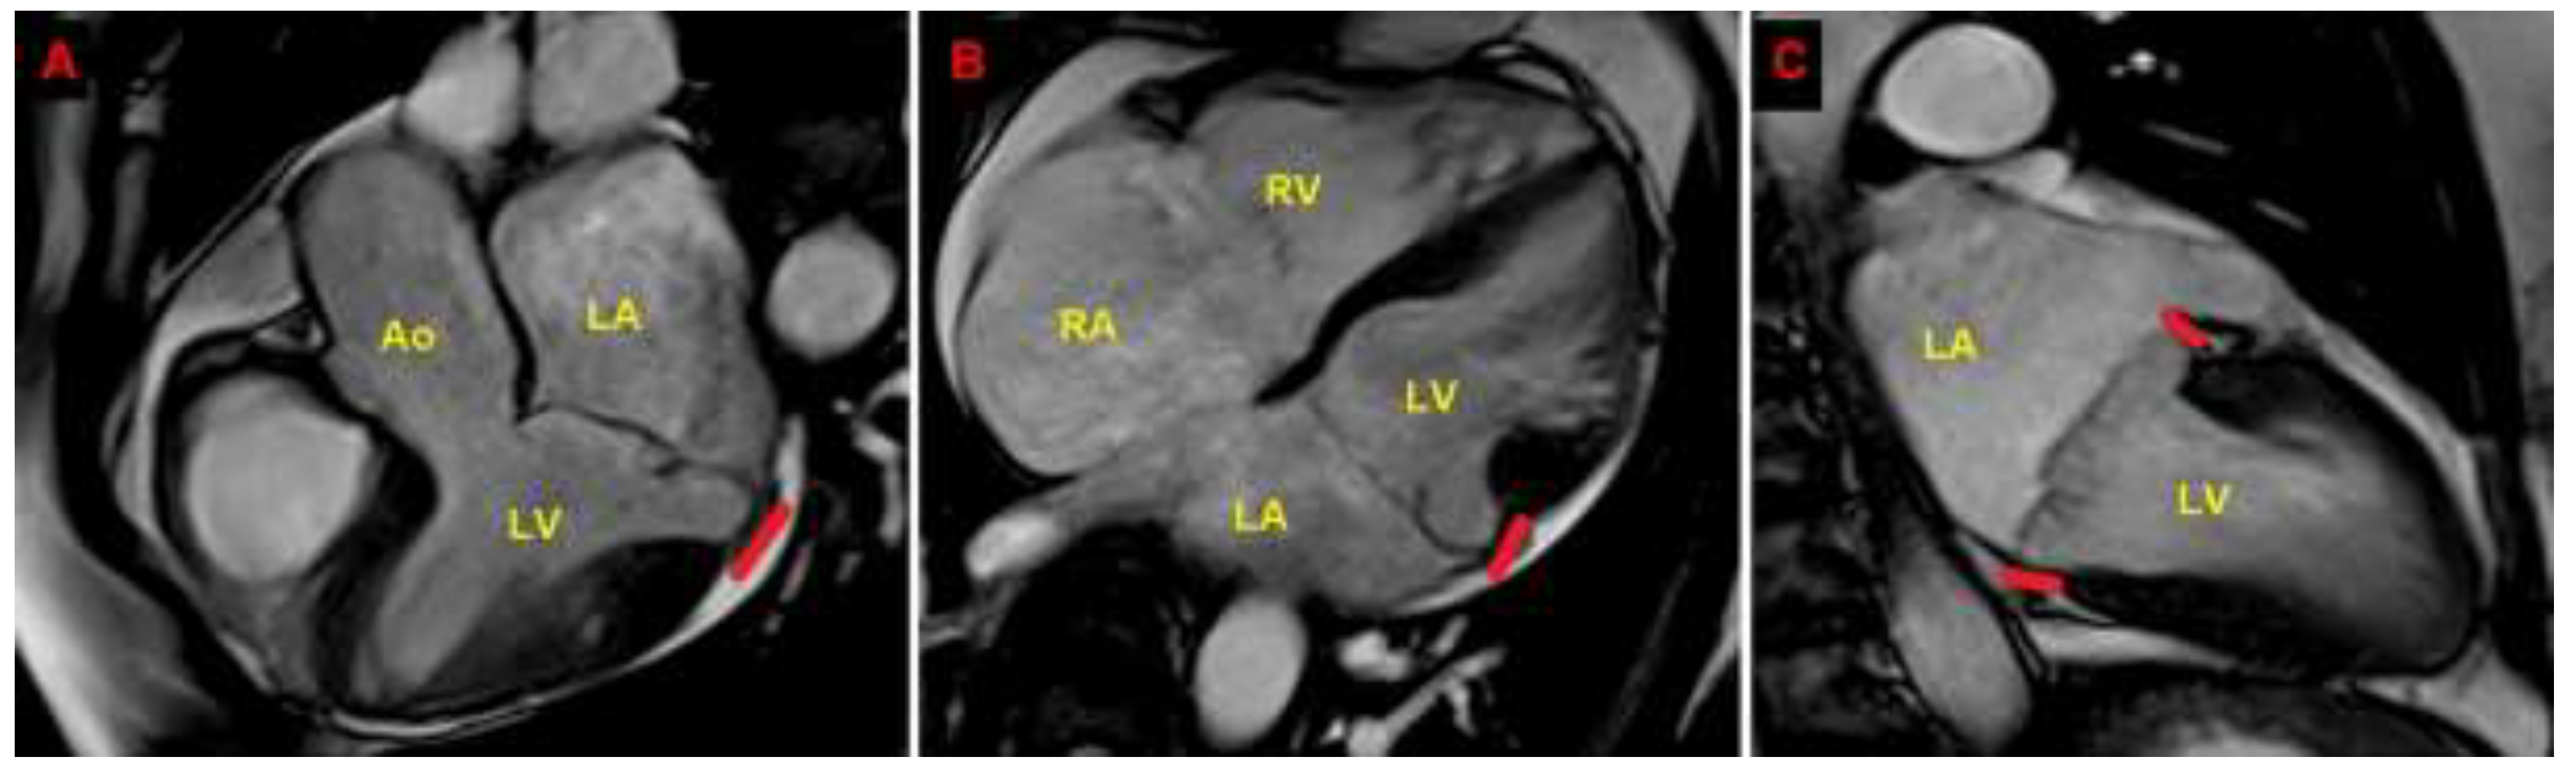

Resting TTE measurements revealed: normal cardiac chambers cavity sizes (left ventricular end-diastolic diameter = 46 mm, right ventricular basal end-diastolic diameter = 33 mm, left atrial antero-posterior end-systolic diameter = 40 mm, right atrial longitudinal diameter 50 mm), grade 1 LV diastolic dysfunction and normal biventricular systolic function [left ventricular ejection fraction (LVEF) estimated with the biplane Simpson's method = 60%; tricuspid annular plane systolic excursion (TAPSE) = 27 mm]; the aortic valve was tricuspid with normal function; a MVP with myxomatous degeneration of both leaflets and moderate mitral regurgitation (MR) was observed; a concomitant MAD was detected from the parasternal long-axis view (systolic infero-lateral MAD distance = 11 mm), from the apical four-chamber view (systolic antero-lateral MAD distance = 9 mm) and from the apical two-chamber view (systolic infero-medial MAD distance = 9 mm and systolic anterior MAD distance = 6 mm) (Figure 2); the estimated systolic pulmonary artery pressure (sPAP) was 30 mmHg.

Due to the echocardiographic detection of wide MAD distance and MV floppy degeneration with moderate MR, the patient underwent a diagnostic study comprehensive of TEE, CMR and CCTA. Transesophageal examination (Figure 4), CMR (Figure 5) and CCTA (Figure 6) confirmed the bileaflet floppy MVP, the circumferential extension of MAD and the moderate degree of MR. All the imaging techniques were concordant on the MAD presence and its extent.

Figure 5. Cardiac magnetic resonance. MAD assessment at end-systole from the three-chamber view (A), four-chamber view (B) and two-chamber view (C). The bold red line indicates the MAD distance. Ao, aorta; LA; left atrium; LV, left ventricle; MAD, mitral annular disjunction; RA, right atrium; RV, right ventricle. (A) is reproduced from the paper 10.3390/jcm14051423.